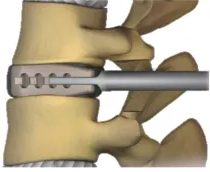

腰椎変性すべり症や分離症、変性側弯症などの治療で行われる腰椎後方椎体間固定術(PLIF)は、腰部の後方から切開し脊椎を露出する一般的な手術方式です。それと異なり、KLIFは内視鏡を用いた椎間固定術であり、MED法を応用したME-LIFとFESS法を応用したPET-LIFがあります。(手術の呼び方は施設のよって異なり統一されていません。当院ではこのように呼んでいます。)これらの特徴としては内視鏡を利用することで手術の低侵襲化が可能となり、従来どおりの手術に比べ早期離床・早期リハビリテーション・早期退院が可能であるうえに術後感染や術後血腫などが従来の術式と比較して低減できるメリットがあると考えています。

Kambin三角と呼ばれる部位から椎間板に達します。

必要に応じてその周囲の骨を削ります。椎間板を切除します。

できたスペースに人工の骨やスペーサーを入れます。

スクリューで最終固定します。